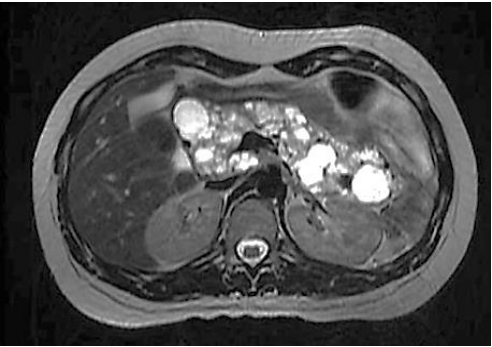

Paciente realiza ressonância magnética que individualiza múltiplas formações císticas pancreáticas, conforme a imagem a seguir:

Fonte: Arquivos Brasileiros de Endocrinologia e Metabologia, v. 43, n. 5, out. 1999.

Nesse caso, o paciente não possui maior risco de desenvolver: